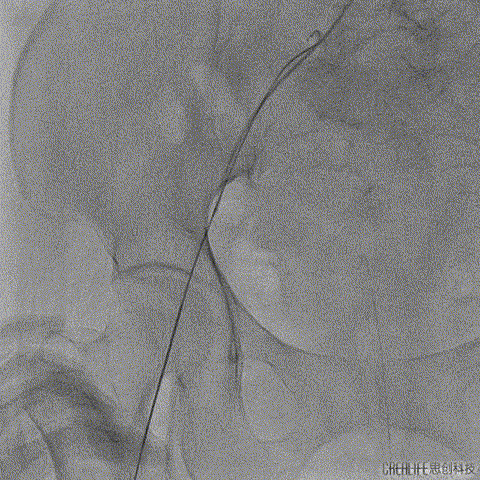

释放到工作位后多角度观察左右冠脉血流灌注情况、瓣膜释放形态及植入深度,确认没问题后再缓慢脱钩完全释放,最终造影显示瓣膜形态、位置良好,冠脉血流灌注正常,微少量瓣周漏;

瓣膜缓慢脱钩完全释放

术后根部造影

术后外周血管造影检查,确认未产生血管并发症。